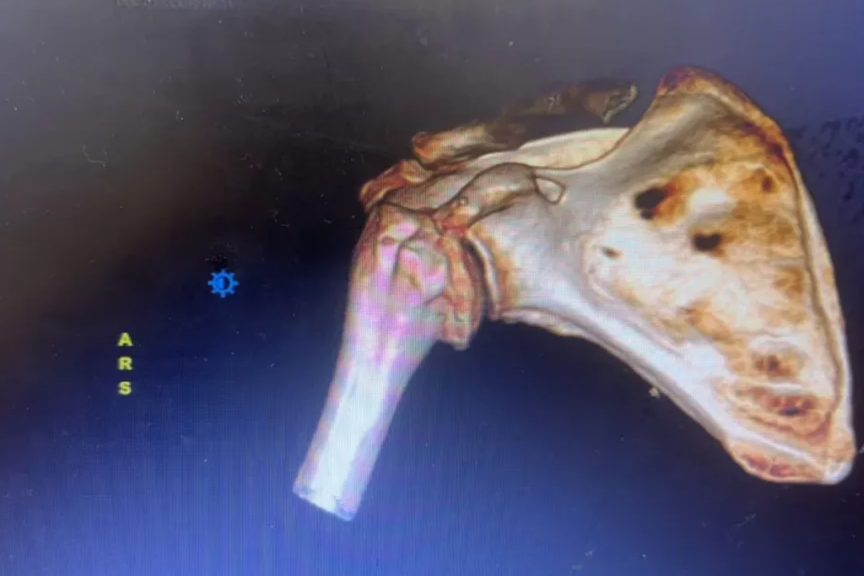

走路摔断肩膀,南医大三附院(常州二院)反肩置换术为患者 「肩」 赋新生

2026-03-19